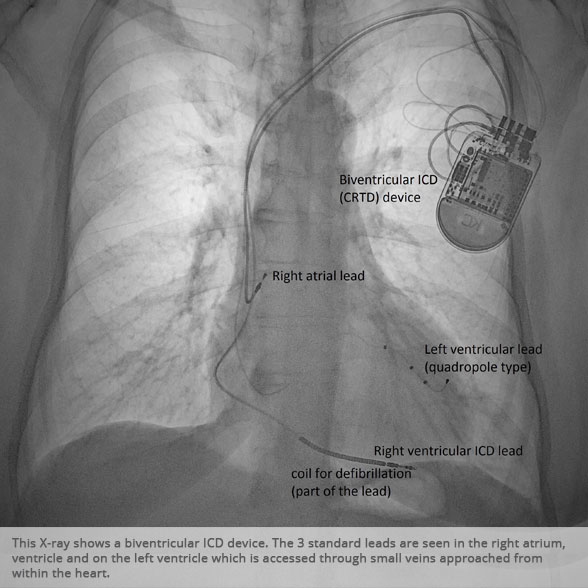

Biventricular ICD (CRTD) Biventricular ICD (CRTD)

Biventricular ICD (CRTD) device Biventricular ICD (CRTD) device

BI-VENTRICULAR PACEMAKERS

Bi-ventricular pacemakers are used for the treatment of suitable patients with heart failure who are already on medication but who suffer from a lack of synchrony between the right and left ventricular contraction. This is most commonly caused by an electrical delay (left bundle branch block LBBB) in transmission of signals to the main pumping chamber (called the left ventricle) and is relatively common in patients with advanced heart failure. This delay process commonly worsens the symptoms of heart failure and it is not generally influenced by medication alone.

Although not all patients universally respond to bi-ventricular pacing (or cardiac resynchronisation therapy/CRT), patients with more advanced dys-synchrony tend to experience remarkable improvement. Bi-ventricular ICDs have the additional benefit of recognising life threatening arrhythmia and deliver both fast pacing bursts or shocks to restore normal heart rhythm.

ICDs

ICDs are used to treat life threatening arrhythmia emerging in the main pumping chambers of the heart (the ventricles). They are offered to patients deemed at risk of such ventricular arrhythmia (primary prevention), for example those who require intervention as a result of significant ventricular scarring after heart attacks, or patients who have been fortunate to survive a cardiac arrest (secondary prevention).

There are established risk stratification algorithms we use to detect patients who may benefit from ICD treatment. ICDs will deliver both fast pacing bursts and shocks to terminate life threatening arrhythmia.